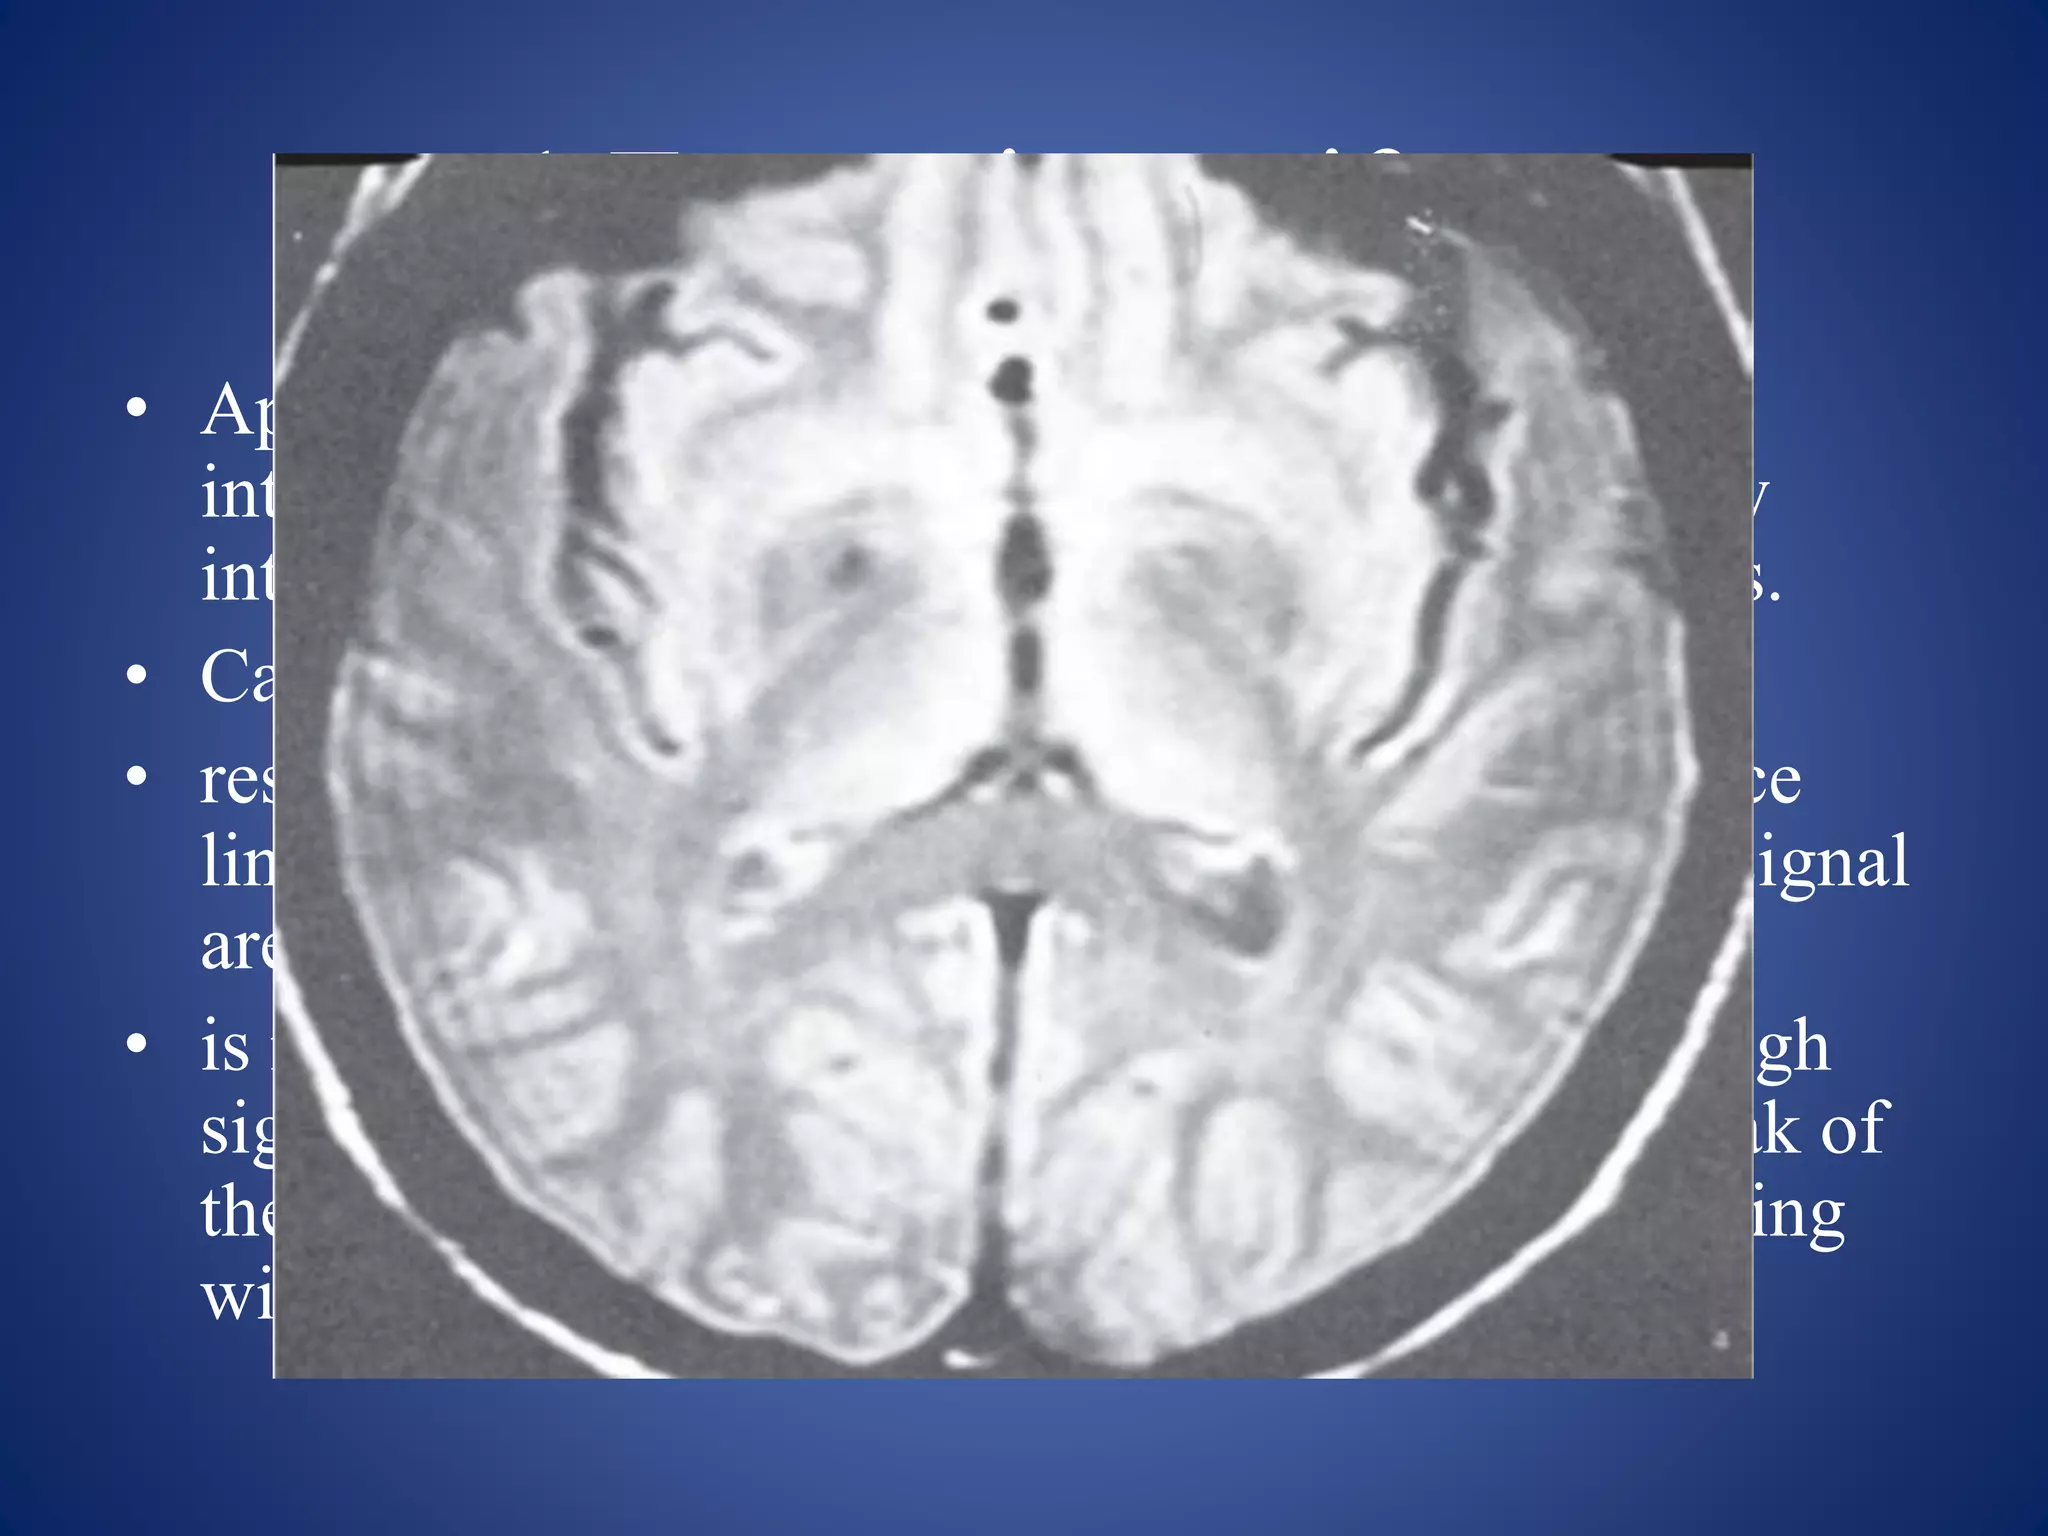

5.Central point artifact

• Appearance: appears as a focal dot of increased or

decreased signal in the exact centre of the image

often with a surrounding ringing artifact

• This artifact was originally misinterpreted as a

multiple sclerosis plaque or a lacunar infarction

• Causes:

Constant offset of DC voltage in the receiver.

After FFT, the constant offset gives the bright dot

at the centre of image

Remedies

• Scanners have compensation software to avoid this

problem (DC Correction, Baseline Correction

• doubling the acquisition time.

• In case of failure, technical assistance is required.

• Repeating the sequence

• Maintaining constant temperature in scanner

• Software to estimate DC offset and adjust the data in K-

space

• Recalibration of the receiver and software correction